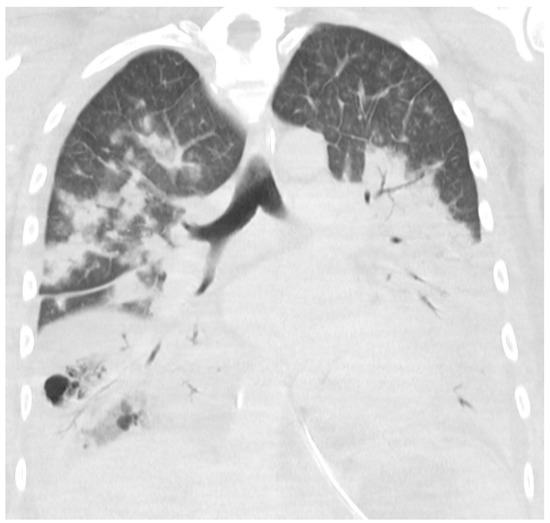

Transthoracic echocardiography showed a left ventricular ejection fraction of 40%. No other abnormalities and no signs of endocarditis were found. A CT scan of the cerebrum, neck, chest, abdomen, and pelvis showed massive bilateral lung infiltrates, atelectasis, and ARDS changes with small amounts of pleural fluids and ascites. No abscesses or infectious foci outside the lungs were found. Figure 2 shows a CT scan of the chest 4 days after admission.

Figure 2. CT scan of the chest with coronal reconstruction. Massive bilateral consolidation with air bronchogram and minimal pleural effusion at day 4.